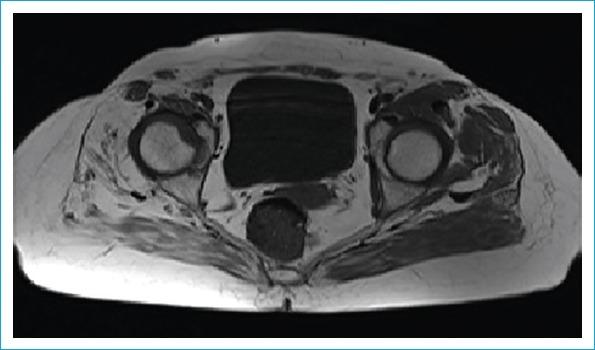

Developmental dysplasia of the hip (DDH) is still one of the biggest orthopedic problems in the world. Global poverty and refugee crises have led to it becoming a greater issue even in developed nations. Early diagnosis and effective treatment of DDH are required to prevent the possibility of arthrosis, limb shortening, pelvic asymmetry, and vertebral scoliosis. In late cases, surgery is the only choice for correction. Direct radiography has been used for many years and continues to have an important role, though ultrasonography is the primary source for early postnatal screening. Although magnetic resonance imaging (MRI) has become an important modality to provide sectional imaging in many cases, in late-period dysplasia, computed tomography (CT) and three-dimensional (3D) CT are preferred because it can more effectively demonstrate the cortical bony structures. The aim of this review was to demonstrate the effectiveness of 3D CT and multiplanar reconstruction based on previous studies.

发育性髋关节发育不良(DDH)仍然是全球最严重的骨科问题之一。全球贫困和难民危机导致即使在发达国家,这一问题也日益严重。为预防关节病、肢体缩短、骨盆不对称和脊柱侧弯的发生,需要对DDH进行早期诊断和有效治疗。在晚期病例中,手术是唯一的矫正选择。直接X线摄影已使用多年且仍发挥着重要作用,不过超声检查是出生后早期筛查的主要手段。尽管磁共振成像(MRI)在许多情况下已成为提供断层成像的重要方式,但在晚期发育不良中,计算机断层扫描(CT)和三维(3D)CT更受青睐,因为它们能更有效地显示皮质骨结构。本综述的目的是基于以往研究展示3D CT和多平面重建的有效性。